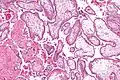

Micrograph showing chorionic villi. Intermediate magnification. H&E stain.